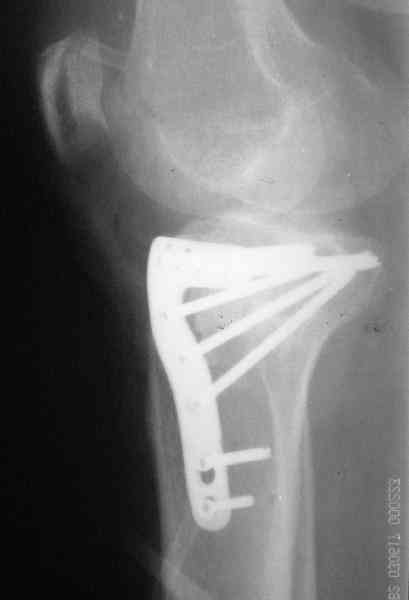

Уважаемый Абдурашид. Если нет противопоказаний , то из оперативных способов, я бы рекомендовал следующие: Полное замещение наружного мыщелка аллотрансплантатом либо открытая репозиция с элевацией и замещение дефекта ауто или аллокостью. В Ваших условиях , я бы рекомендовал второй способ. Во-время элевации необходимо разъединить фрагменты со стороны сустава ( надсечь скальпелем по линиям перелома, а затем тонким остеотомом их разъединить. При помощи долота произвести неполную остеотомию ( захватите не менее 1,5 - 2 см губчатой кости и поднять фрагменты, визуально отрепонировать и фиксировать 2-3 спицами. Дефект заместить костным ауто или аллатрансплантатом. Окончательная стабилизация пластиной ( лучше с угловой стабильностью, либо АВФ - позволит спокойно устранить угловую деформацию.

Через 3 месяца после перелома все еще можно выделить отломки, очистить от костной мозоли и и восстановить анатомию суставной поверхности. Фиксировать компрессионными шурупами. Важно помнить, что наружный мыщелок должен быть на 4-5 мм выше внутреннего. Передняя крестообразная связка обычно остается с частью кости и важно фиксировать ее проволокой по Ли. После восстановления суставной поверхности весь комплекс суставной поверхности нужно фиксировать к диафизу, можно использовать пластинку с фиксированными шурупами с наружной поверхности или две обычные с двух сторон или аппарат Илизарова. Важно сохранить задний наклон плато приблизительно 7 градусов. При закрытии доступа бугристость б.б кости фиксировать двумя шурупами. Важно добиться стабильности для максимально ранней разработки. Операция сложная, но интересная.

Наш план; доступ как подсказал Michael, по возможности репозиция, костная аутопластика дефекта метафиза, винты и спицы, АВФ и умеренная дистракция с шарнирными стержнями, и ранная пассивная разработка. Операцию планируем на следуюшей недели.